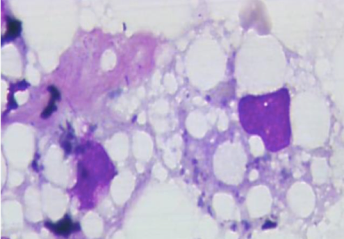

You notice intra and inter-hepatic vacuoles. What does this indicate

Hepatic lipidosis

Is this a normal liver? What’s it stained with?

No, hepatic lipidosis